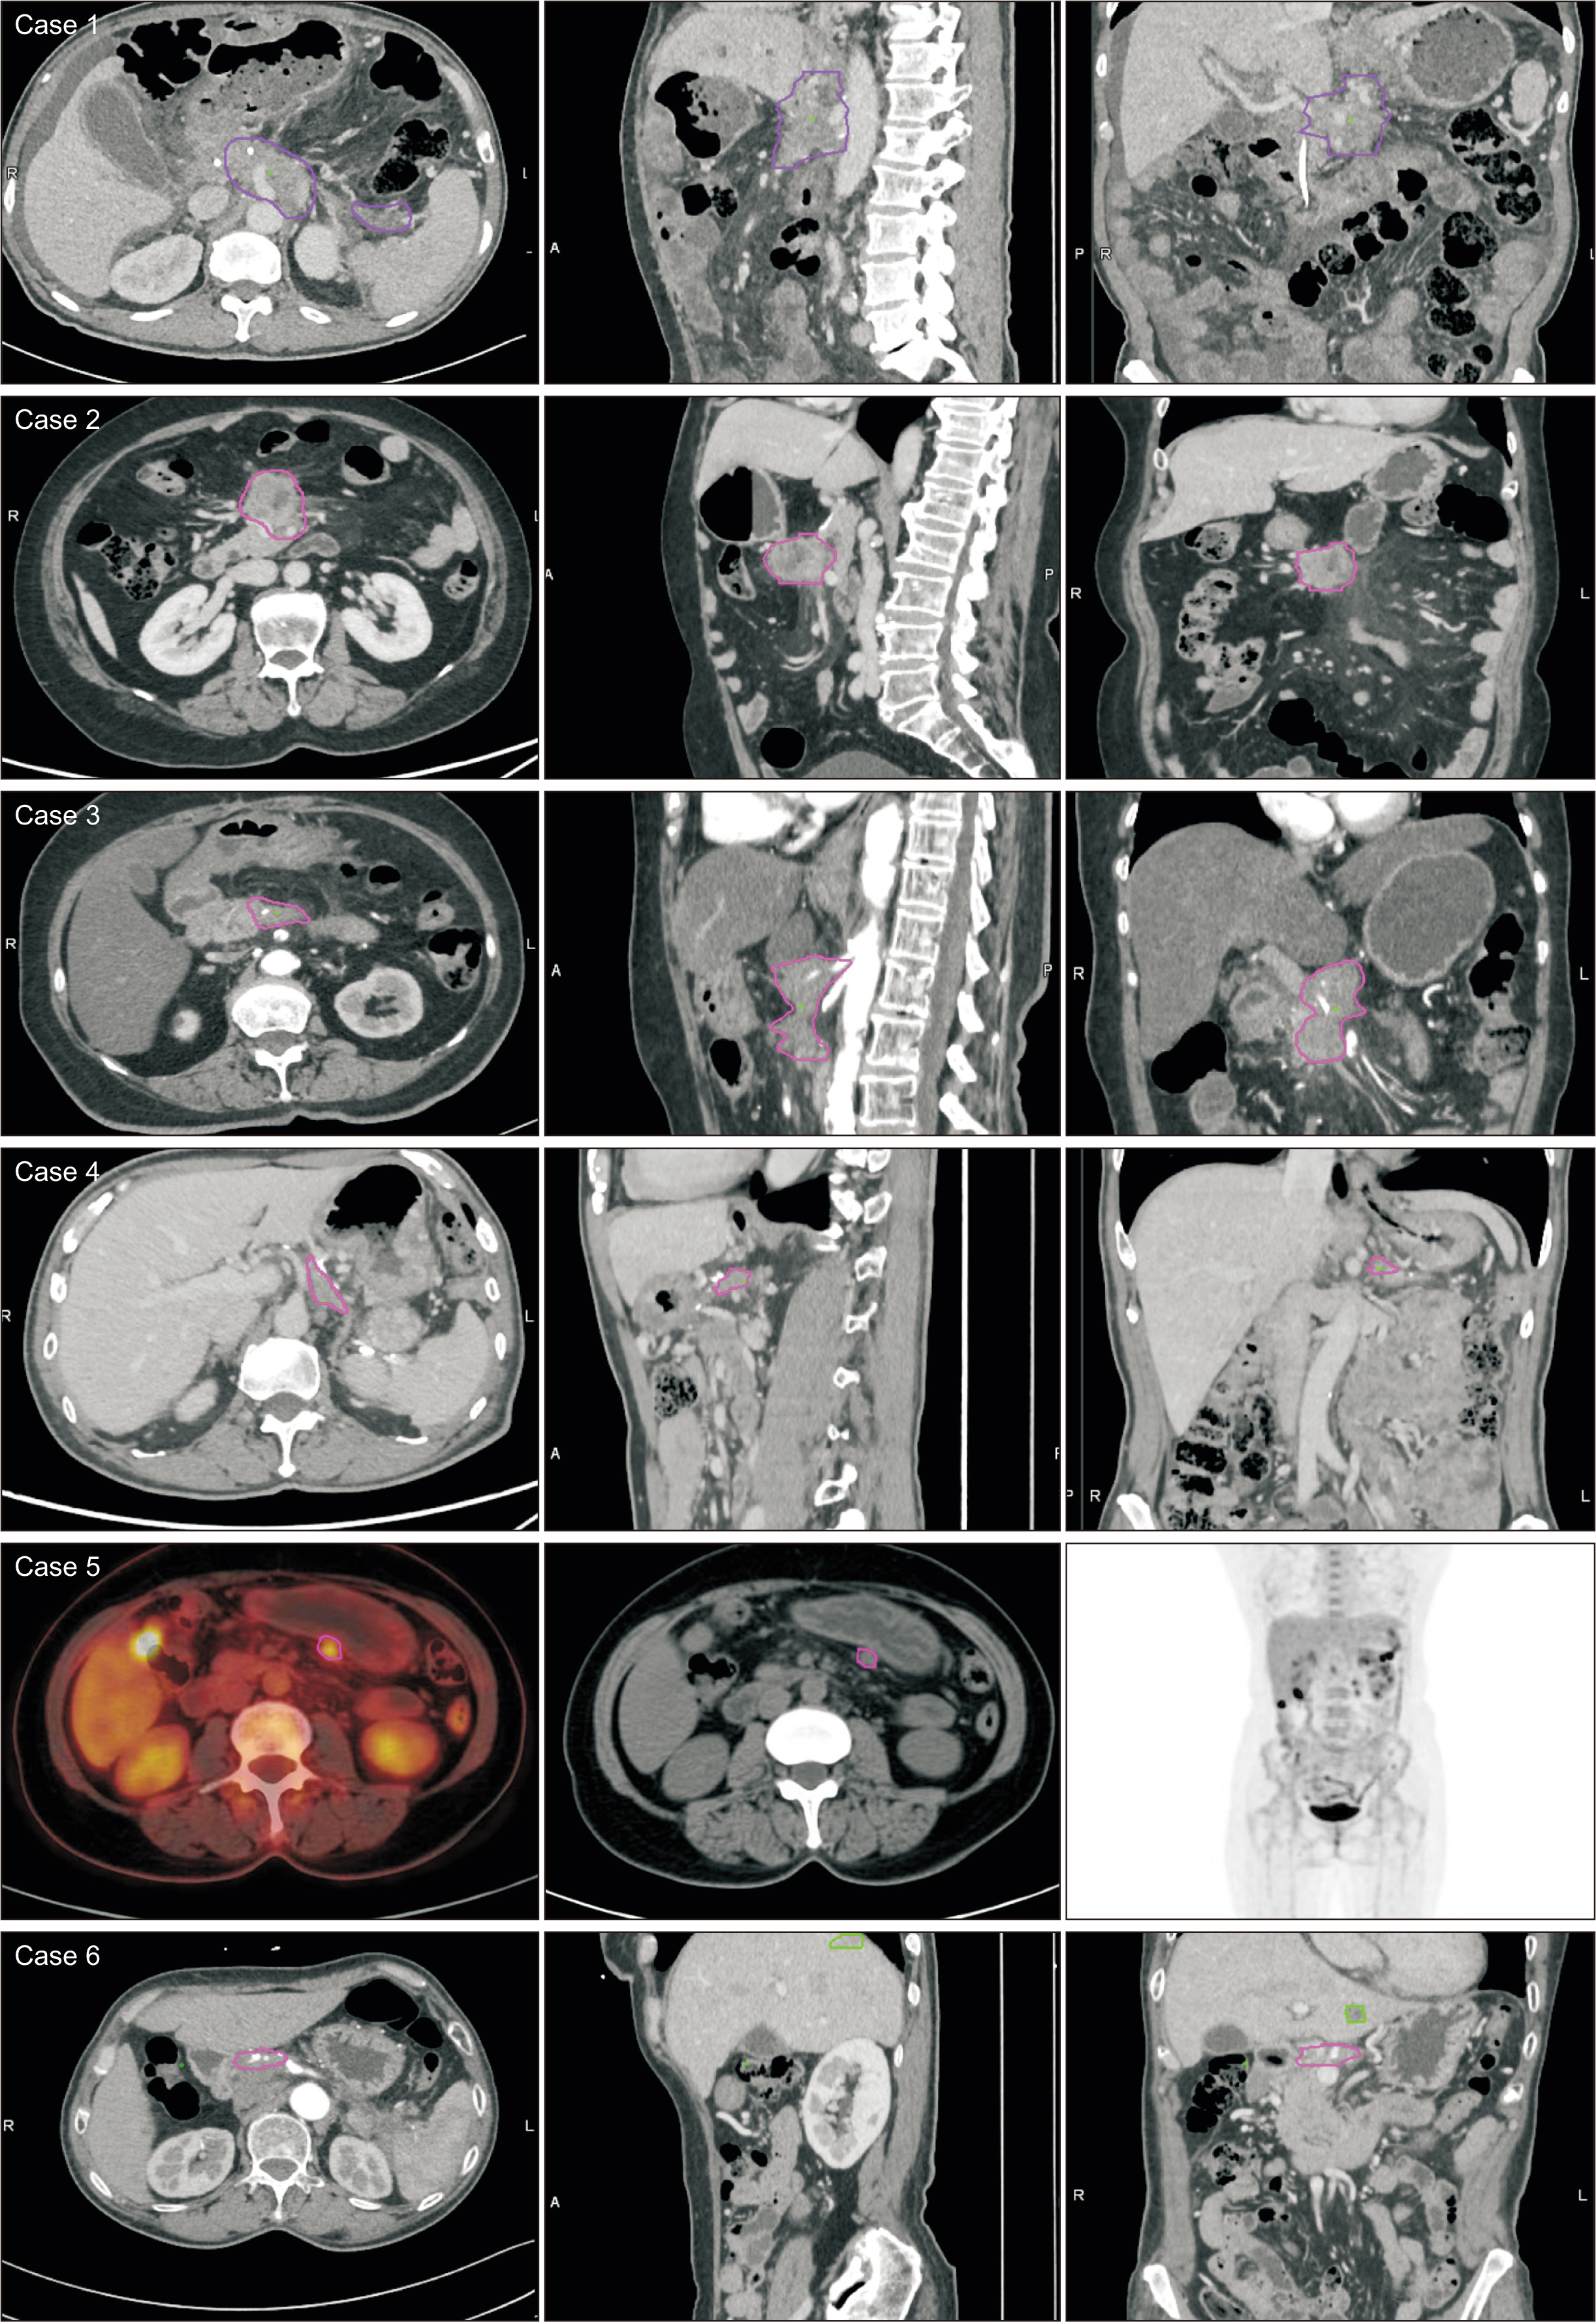

Both groups exhibited similar demographic, intraoperative, and pathological characteristics, with the exception of a reduced number of total lymph nodes (p = 0.006) in the SPDP group. There were no significant differences in the rates of postoperative complications, recurrence, or metastasis. Local recurrence predominantly occurred in the central region as opposed to the spleen region. There were no cases of isolated recurrences in the splenic region. Median overall survival and recurrence-free survival times were 51.5 months for SPDP vs 30.5 months for DPS and 18.7 months vs 16.8 months, respectively (p > 0.05). The incidence of partial splenic infarction and left-side portal hypertension in the SPDP group was 28.6% (6/21) and 9.5% (2/21), respectively, without necessitating splenic abscess puncture, splenectomy, or causing bleeding from perigastric varices.